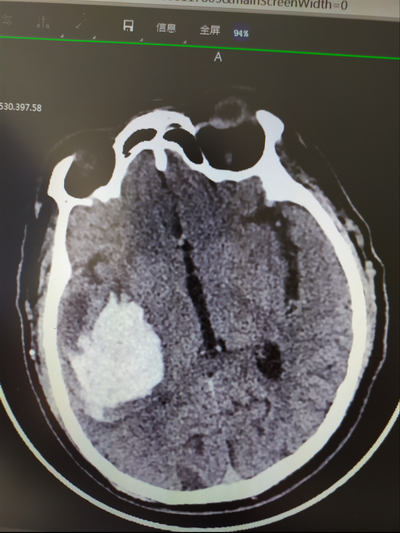

患者男性,66歲,因突發(fā)頭痛伴左側(cè)肢體活動不靈活4小時余來診。診斷:出血性腦卒中(右側(cè)基底節(jié)區(qū)腦出血,出血量大約40ML),查體:神志清楚,GCS評分13分,左側(cè)肢體肌力3級,病理征陽性。患者右利手,既往有高血壓病史多年,血壓控制不理想。

術(shù)前CT顯示